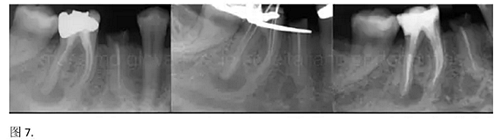

開(kāi)髓后預(yù)敞、探查根管、建立直線通路是根管機(jī)械預(yù)備的第一步。在這些階段中,醫(yī)生可能會(huì)經(jīng)常遇到一些困難。這些難題包括器械折斷、臺(tái)階形成、根管歧坡或根管拉直、帶狀穿孔、根尖穿孔、根尖肘形、根尖堵塞。所有這些錯(cuò)誤可導(dǎo)致根管系統(tǒng)清潔不完善從而降低牙髓治療成功率。

結(jié)論:本文的目的是描述一種旨在優(yōu)化根管根尖部分預(yù)備的預(yù)敞技術(shù)。根管頸部或冠方的早期預(yù)敞對(duì)于減少初尖銼直徑和根尖部根管直徑之間的差異至關(guān)重要。大量研究表明,手用或機(jī)用器械預(yù)敞根管能顯著減少器械折斷的發(fā)生率。下一篇文章將描述如何建立可重復(fù)的引導(dǎo)路徑。而引導(dǎo)路徑是指鎳鈦器械可沿著光滑根管壁輕易地滑行至工作長(zhǎng)度的通路。